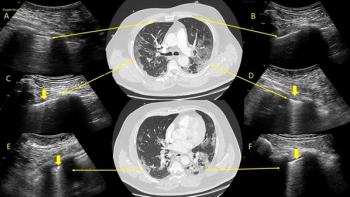

Side-by-side images show lung ultrasound pinpoints same findings as low-dose chest CT.

After 2.5 hours, providers could successfully identify lungs with pathological patterns indicative of viral infection.